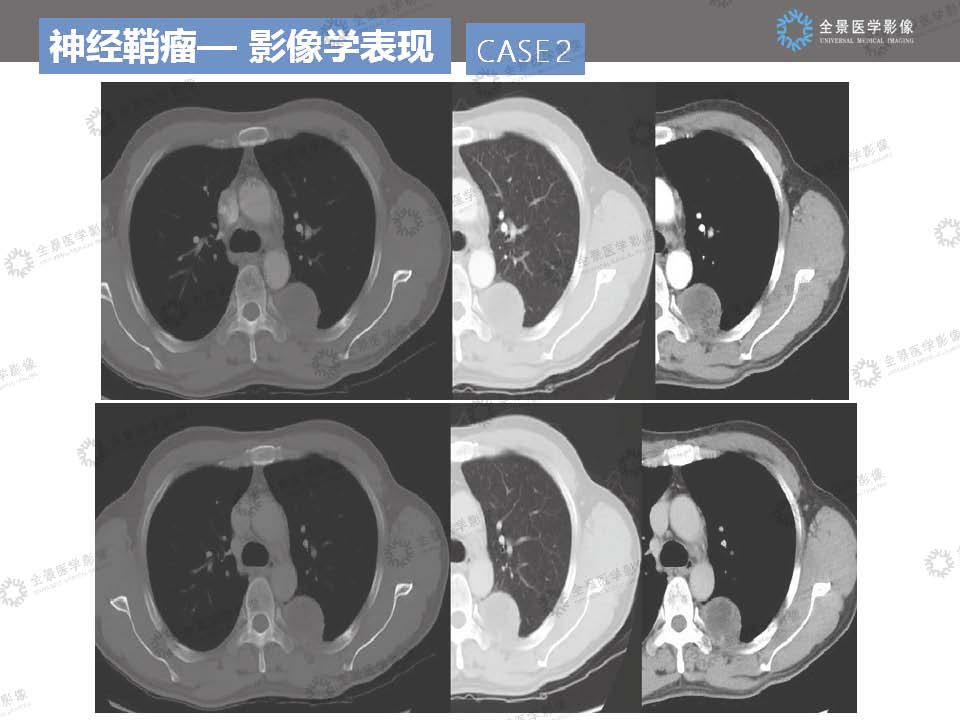

神经鞘瘤读片病例